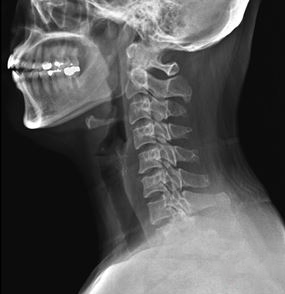

그래서 바로 초음파 검사와 X-ray를 시행했어요.

거기에 목디스크 감별진단까지!

그림2.png

결과는?

목디스크였습니다

콕병원에서는 이런 이유로 초음파 검사를 적극 활용하고 있어요.

X-ray로는 보이지 않는 인대, 관절, 근육의 상태를

실시간으로 확인할 수 있거든요.